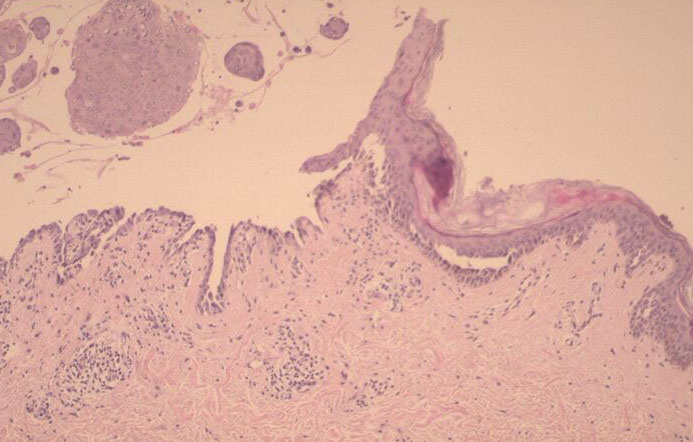

The earliest recognized change may be either eosinophilic spongiosis rarely or, more commonly, “spongiosis” in the lower epidermis . This spongiosis may actually represent the earliest manifestation of acantholysis rather than true spongiosis as defined earlier. Acantholysis leads first to the formation of clefts and then to blisters in a predominantly suprabasallocation . The intraepithelial acantholysis may extend into adnexal structures or occasionally be higher in the stratum spinosum. The basal keratinocytes, although separated from one another through the loss of attachment, remain firmly attached to the dermis like a “row of tombstones.” Within the blister cavity, the acantholytic keratinocytes, singularly or in clusters, have rounded condensed cytoplasm about an enlarged nucleus with peripherally palisaded chromatin and enlarged nucleoli. In some patients, there are varying quantities of antidesmoglein 1 and antidesmoglein 3 antibodies, leading to variable planes of acantholysis. There is little inflammation in the early phase of blister formation. If present, it is usually a sparse, lymphocytic perivascular infiltrate accompanied by dermal edema. However, if eosinophilic spongiosis is apparent, numerous eosinophils may infiltrate the dermis. The phenomenon of eosinophilic spongiosis occurs occasionally in other blistering diseases, particularly in their early phases, including acute contact dermatitis, pemphigus foliaceus, bullous pemphigoid, herpes gestation is, drug eruptions, spongiotic arthropod bite reactions, and transient acantholytic dermatosis. Several important changes ensue as the lesions age. First, a mixed inflammatory cell reaction consisting of neutrophils, lymphocytes, macrophages, and eosinophils may develop. Because of the instability of the blister roof, erosion and ulceration may occur. Older blisters may also have several layers of keratinocytes at the blister base because of keratinocyte migration and proliferation. Last, there may be considerable downward growth of epidermal strands, giving rise to so-called villi (Fig. 9-9D). The evaluation of patients with only oral lesions is difficult, because intact blisters are rarely encountered due to the trauma of mastication, and biopsies may show only erosion and ulceration. Indeed, it is best to sample the edge of a denuded area with intact mucosa in an attempt to demonstrate the typical pathologic changes. Clinicians frequently cannot distinguish between an ulcer and the intact mucosa, as both are often white and shaggy. In patients with only oral lesions, biopsies of intact oral mucosa for DIF testing are more sensitive than biopsies of lesions for routine light microscopic evaluation. Therefore, biopsy from the normal maxillary and upper buccal mucosa is necessary when there is extensive ulceration. Cytologic examination using a Tzanck preparation is useful for the rapid demonstration of acantholytic epidermal keratinocytes in the blisters of pemphigus vulgaris. For this

purpose, a smear is taken from the underside of the roof and from the base of an early, freshly opened bulla. Giemsa stain is applied with subsequent rinsing and air-drying.

Because acantholytic keratinocytes are occasionally seen in various nonacantholytic vesiculobullous or pustular diseases as a result of secondary acantholysis, cytologic examination represents merely a preliminary test and should not supplant histologic examination.